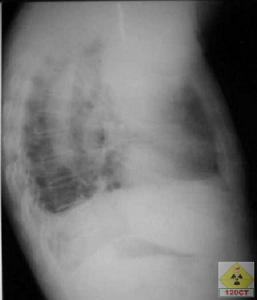

X線檢查所見,內型呈半圓形充盈缺損,邊緣整齊,有時其中央可見臍樣的潰瘍龕影;外型表現為受壓,壁黏膜完整,皺襞有拉平現象。檢查可見黏膜下腫塊的特徵,如有潰瘍時,從該處取活檢較易確診。